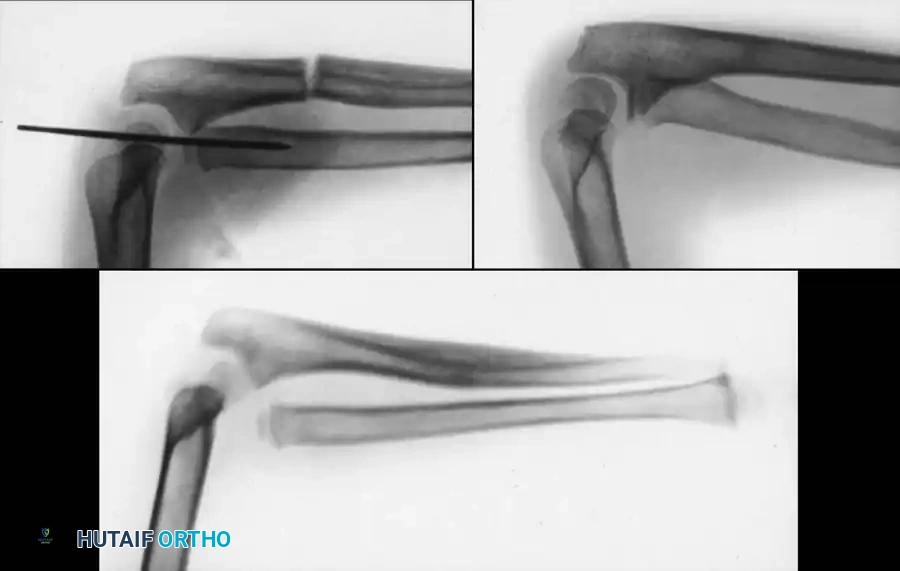

FRACTURES OF THE MIDDLE THIRD (DIAPHYSEAL) OF THE FOREARM

Remodeling Potential and Acceptable Alignment

Diaphyseal fractures of the radius and ulna require careful assessment. Vittas et al. and Karaharju et al. emphasized that while the physis drives remodeling, this potential decreases significantly in late childhood and is less pronounced in the midshaft compared to the distal metaphysis.

Price et al. established widely accepted criteria for conservative management of diaphyseal both-bone fractures in skeletally immature patients. They concluded that anatomical alignment is ideal, but the following parameters are acceptable and will not lead to severe functional disability:

* Up to 40 degrees of malrotation.

* Up to 10 degrees of angulation.

* Complete displacement (bayonet apposition), provided alignment is maintained.

Image

Indications for Operative Treatment

According to Weber et al. and Nielson and Simonsen, operative treatment for middle-third fractures is indicated in the following scenarios:

1. Open fractures requiring surgical débridement.

2. Older children (approaching skeletal maturity) where remodeling potential is exhausted. Fuller and McCullough noted that gross malunion does not correct in girls older than 8 years or boys older than 10 years.

3. Irreducible fractures due to soft-tissue interposition.

4. Multiple refractures occurring within a short timeframe.

5. Failed closed reduction after multiple attempts.